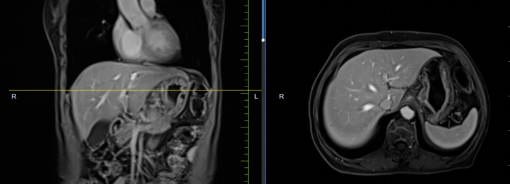

患者孟某某,女,73歲,因腹部不適行胃鏡及PET-CT,發(fā)現(xiàn)胃癌、骨、肺、肝多發(fā)轉(zhuǎn)移,胃壁厚約2cm,腹腔大淋巴結(jié)約3cm,肝最大轉(zhuǎn)移灶約3cm。同樣6周期化療+免疫,聯(lián)合中醫(yī)中藥后病灶明顯縮小,現(xiàn)已進(jìn)入維持治療階段,身體狀況恢復(fù)至常人水平。

治療前